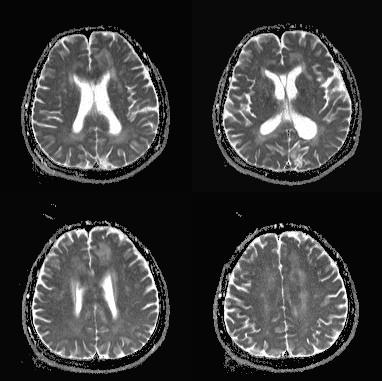

影像资料:

•急性期表现为胼胝体弥漫性肿胀,T1WI呈稍低信号,T2WI及FLAIR呈稍高信号,以矢状位观察最佳,可单独累及胼胝体压部或整个胼胝体,DWI呈高信号,ADC图呈低信号,部分患者可观察到脑室周围白质或内囊受累,少见皮层受累,表现为扩散受限,不强化和强化病例均可见到。如果增强扫描可见胼胝体有不同程度强化,呈小灶状或不规则斑片状,系血脑屏障破坏所致(如本例),本例患者处于急性期。

胼胝体压部病变及多发皮层对称性病变,表现为扩散受限

•随着病变进展至亚急性期和慢性期,胼胝体内可出现坏死、囊变,以膝部及压部表现为著。在膝部和体部常表现为中心夹层状异常信号,类似“三明治”状,其境界清楚,据认为这是本病的特点之一。病理检查证实,病变主要对称性侵及胼胝体的中心层,而背、腹层面的组织结构相对完好。主要的组织学所见为脱髓鞘,少突胶质细胞明显减少,而含脂巨细胞大量增多。部分病例在T2加权像上,偶见胼胝体变性、坏死区内出现极低信号,镜下病理显示含脂巨细胞内可见散在或成堆的含铁血黄素分布,可能为T2异常低信号的病理基础。